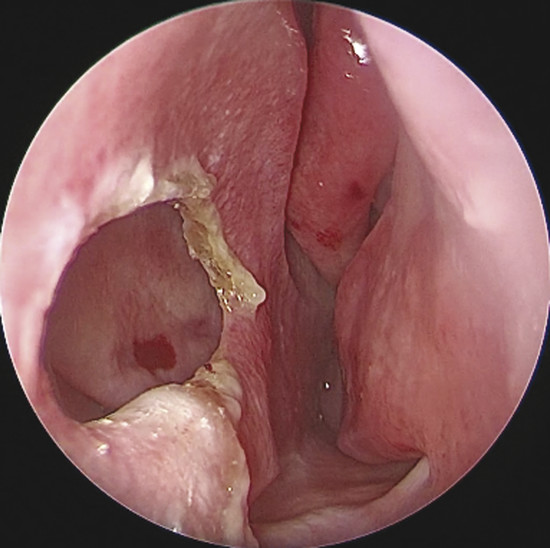

Upon physical examination of the nose, a full diagnosis cannot be made until all crusts have been removed and decongestion of the turbinates has taken place, making it possible to visualize the entire nasal septum. The nasal endoscopy allows appreciating the configuration of the NSP, the presence or absence of adherent crusts on the edges of the defect (Fig. 6‑1), any easily bleeding areas (Fig. 6‑2), and the state of the remaining mucosa, which may present some aspects regarding ischemic conditions (cocaine abuse) (Fig. 6‑3).